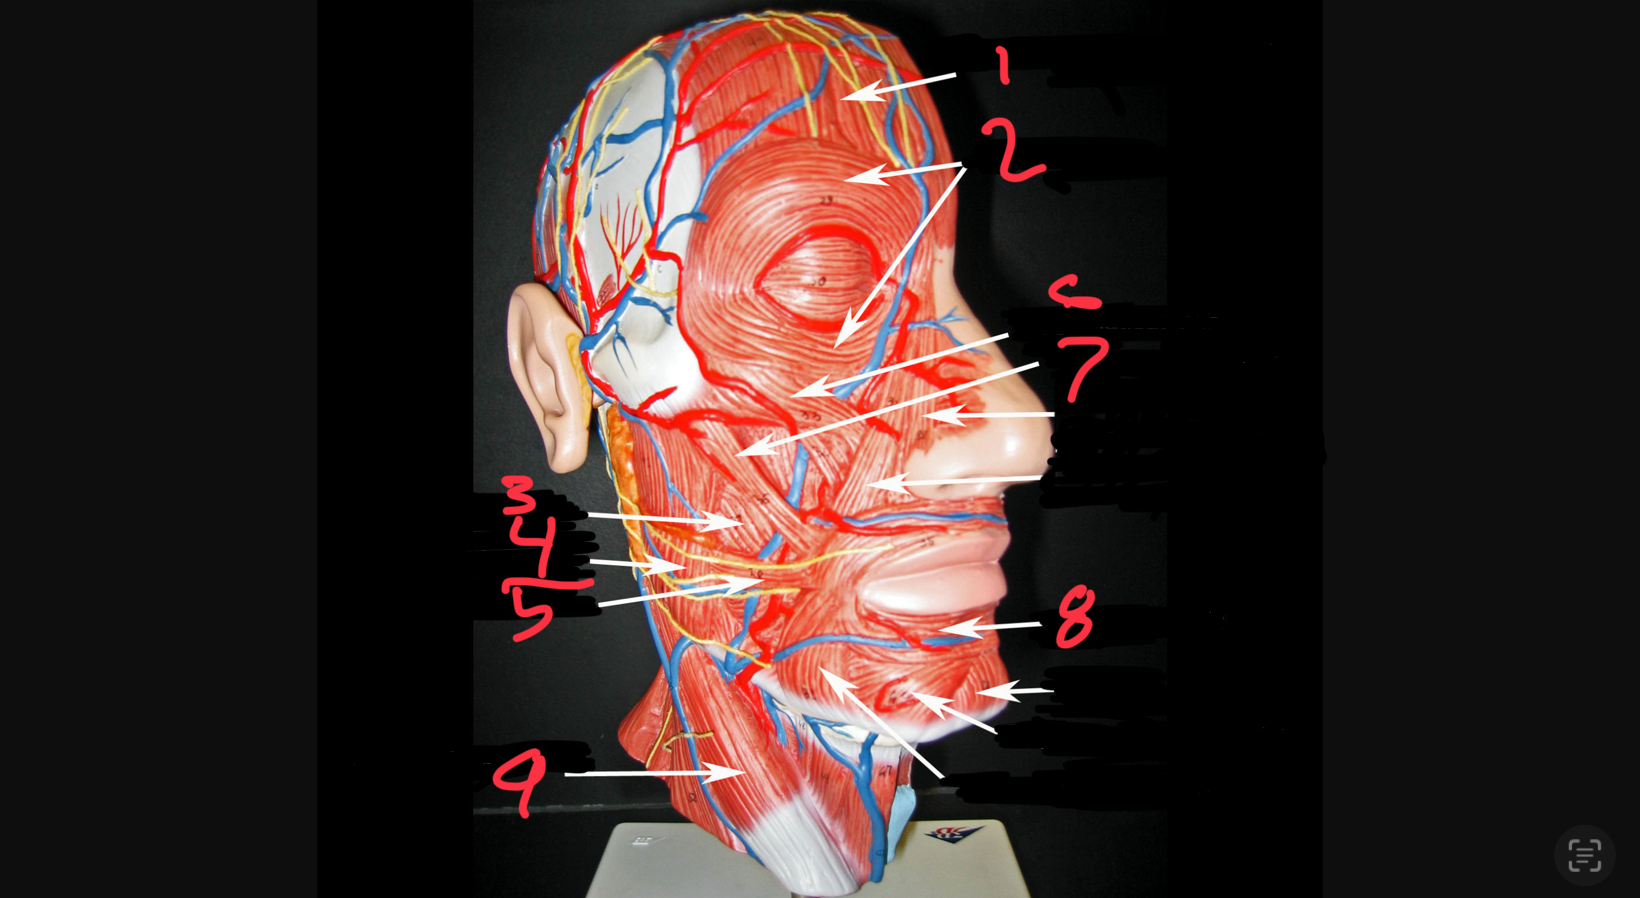

what #1

occipitofrontalis (frontal belly)

what is #2

orbicularis oculi

what is #3

buccinator

what is #4

masseter

what is #5

risorius

what is #6

zygomaticus minor

what is #7

zygomaticus major

what is #8

orbicularis oris

what is #9

sternocleidomastoid